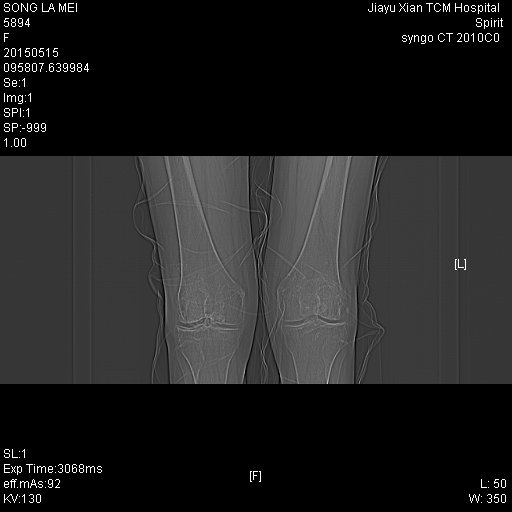

CT50447:女,67Y,膝关节疼痛

无外伤史,膝关节疼痛,各位专家帮忙看下

支持:双膝关节退行性变,右膝关节滑膜骨软骨瘤病并关节积液

双膝关节可见骨质增生硬化变尖改变,右膝关节囊内及周围可见多发骨化结节,部分结节呈蛋壳样,考虑双膝关节退变,右膝关节滑膜骨软骨瘤病。

双膝关节退行性改变,右膝关节滑膜骨软骨瘤病.